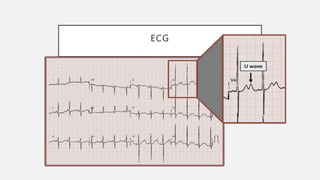

ECG

• ↓segmento ST

• ↓onda T

• ↑onda U (V4-V6)

• ↑duración complejo QRS (grave)

ECG • ↓segmento ST •↓onda T • ↑onda U (V4-V6) • ↑duración complejo QRS (grave)